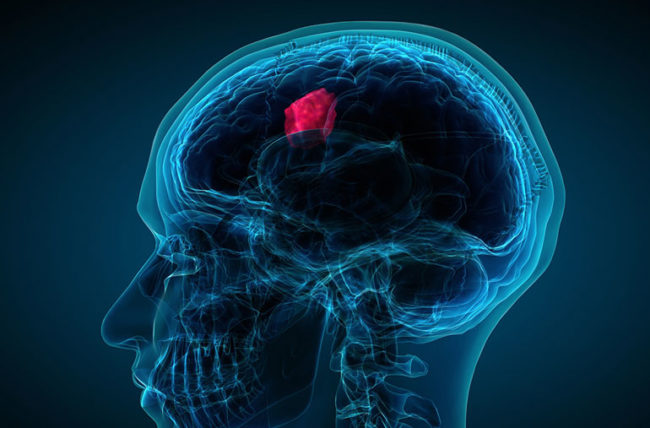

تومور بدخیم مغزی نوعی از سرطان است که در بافتهای مغز یا نخاع رشد میکند. این تومورها شامل سلولهای غیرطبیعی هستند که به سرعت تکثیر شده و میتوانند به نواحی دیگر مغز یا حتی بدن گسترش یابند. برخلاف تومورهای خوشخیم، تومورهای بدخیم مغزی بسیار تهاجمی بوده، به سرعت رشد میکنند و به بافتهای مجاور تهاجم میکنند.

تومورهای مغزی بدخیم انواع مختلفی دارند که شایعترین آنها گلیوبلاستوما است. گلیوبلاستوما شایعترین نوع تومور بدخیم مغزی در بزرگسالان محسوب میشود و با رشد سریع خود شناخته میشود. نوع دیگر، مدولوبلاستوما است که بیشتر در کودکان شایع بوده و در بخش تحتانی مغز به نام مخچه ایجاد میشود.

- محل تومور: تومورهایی که در مناطق حساس مغز قرار دارند، ممکن است جراحی کامل آنها امکانپذیر نباشد.